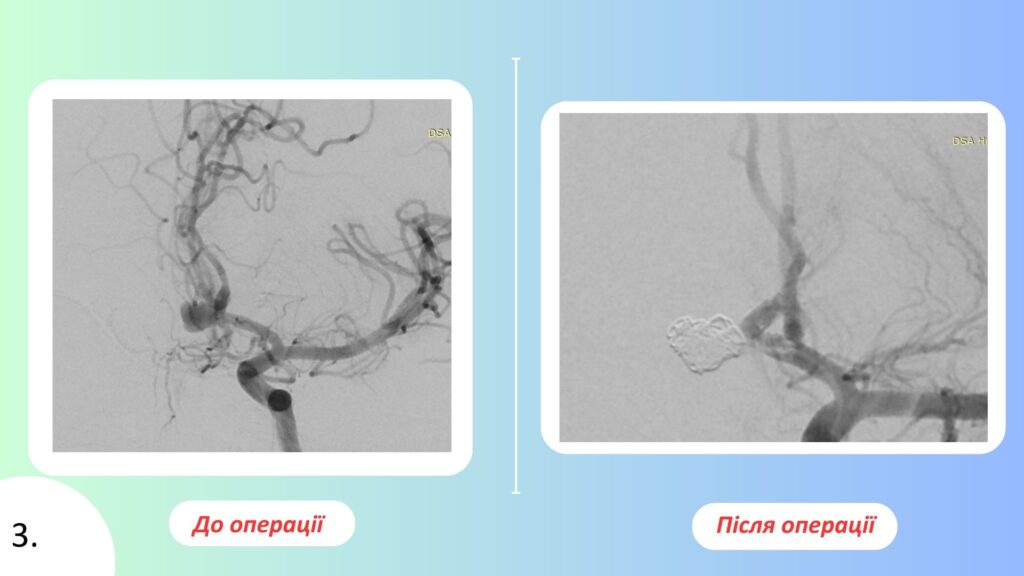

Другий випадок — 42-річний військовослужбовець із мішковидною аневризмою передньої мозкової та передньої сполучної артерій. В анамнезі — субарахноїдальний крововилив унаслідок розриву аневризми. Під час дообстеження ангіографічно підтверджено наявність аневризми з дочірніми камерами. Фахівцями Центру виконано ендоваскулярну оклюзію аневризми мікроспіралями зі стент-асистенцією. Операція та післяопераційний період пройшли без ускладнень, стан пацієнта при виписці — задовільний.